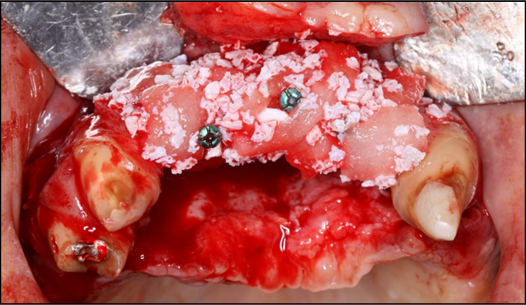

The surgical procedure was done under intravenous sedation using Fentanyl and Versed. Local anesthetic was used and a supra-crestal horizontal incision made on the palatal aspect of the anterior maxilla. A mucoperiosteal flaps were elevated, exposing a severely resorbed ridge of the pre-maxilla (Figure 2). Decortication was conducted with a round carbide bur in order to perforated the cortical aspect of the bone and expose the cancellous bone, to increase vascularity to the recipient site. Three screws were fixed parallel to the adjacent teeth, serving as “tent pole”. The screws had 14 mm length and approximately 6-8 mm of the tenting screws were exposed to the oral cavity (Figure 3). An absorbable collagen sponge (ACS) carrier/matrix was embedded with 12 mg of rhBMP-2 at 1.5 mg/mL (Infuse® Medtronic Sofamor Danek, Memphis, TN, USA) and allowed to absorb for approximately 20 min. The rhBMP-2/ACS was cut into strips, half of the strips were added to the natural bone mineral component derived from bovine bone (Geistlich Bio-Oss® granules small - 0.25 to 1 mm, Geistlich Pharma, Germany). Initially, some strips of rhBMP-2/ACS were placed over the buccal aspect of the residual alveolar ridge of the pre-maxilla, followed by strips mixed with bovine bone (Figure 4). The three screws were fully covered by rhBMP-2/ACS strips. Finally, a titanium mesh was adapted over the entire rhBMP-2/ACS graft and fixed with 2 monocortical screws, one on the buccal aspect and one on the palatal aspect of the ridge, respecting a 2 mm distance from the mesh to the adjacent teeth (Figure 5). Extensive undermining incision was conducted on the apical aspect of the buccal flap in order to achieve primary closure.

Figure 4.Occlusal view of the pre-maxilla after placement of strips of the rhBMP-2/ACS added to the natural bone mineral component derived from bovine bone.